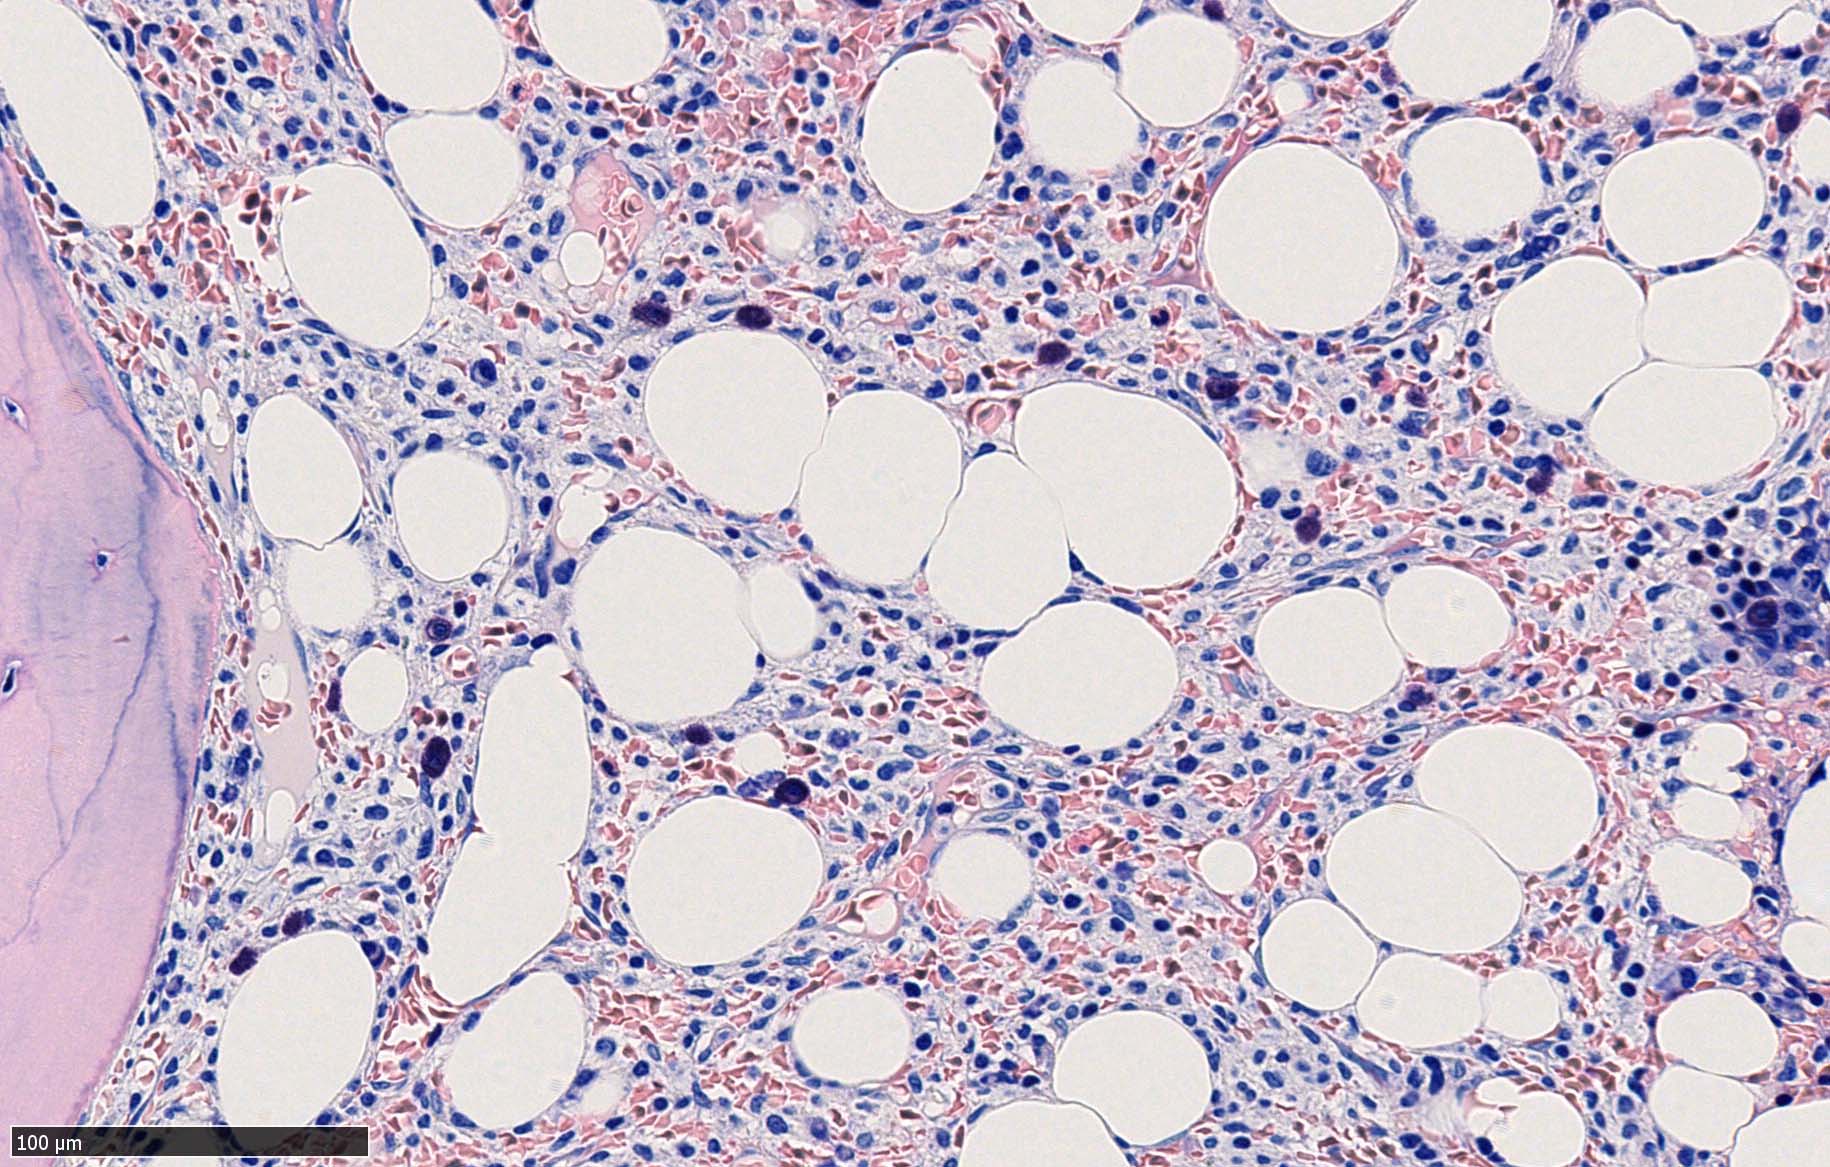

骨髄生検

bone marrow trephine biopsy: dry tapのため骨髄生検が行われる. cellularityは40-80%とhypercellular marrow. 流れのある細胞配列は線維化を疑わせる.

ASD-G 低倍率所見では赤芽球血島は幼若赤芽球の集簇巣が散在する, 顆粒球系細胞(ASDに赤く染色される)は減少,granulopoietic hypoplasiaを呈する.疎な集簇を示すmast cellsの増加がある.

ASD-G陰性の細胞がびまん性に増加しているように見える.

ASD-Giemsa陰性の細胞がシート状に増殖する. 核はクロマチン濃染, 核小体は不明瞭.類円形, 卵円形, くびれを持つ多稜形核, 長円形いびつで屈曲した核, など多彩. 細胞質は淡清色調, 広く淡明. 赤芽球血島は幼若赤芽球のみで形成される異形成像を示す. やや離れて成熟赤芽球が疎な集簇を示す.